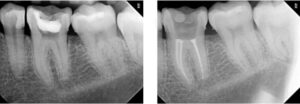

Nas imagens a seguir apresentamos casos: à esquerda, o dente com infecção. À direita, após o tratamento de canal, o dente tratado e preservado (imagem radiopacas mais claras/brancas dentro dos condutos dos canais).